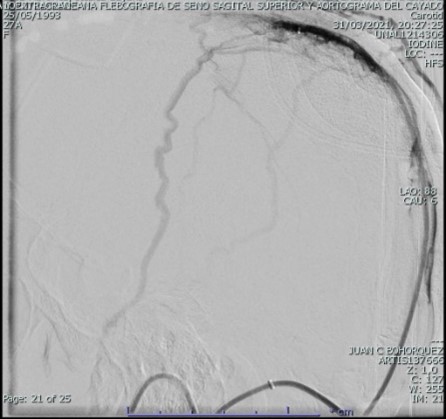

El examen físico inicial sin alteración neurológica; sin embargo dado cuadro clínico se enfoca como cefalea con banderas rojas con sospecha de hipertensión intracraneal, se toma tomografía de cráneo simple con hallazgo de trombosis del seno sagital superior con extensión hacia el seno transverso derecho y hacia la región proximal del seno sigmoideo ipsilateral, con discreto edema difuso de los lóbulos occipital, parietal y región posterior del lóbulo temporal ipsilateral; se inicia anticoagulación con heparina de bajo peso molecular a 1 mg/kg cada 12 horas y se decide caracterización con panagiografía cerebral temprana y evaluar beneficio de neurointervención, la cual muestra extensa trombosis de senos durales, longitudinal superior en sus dos tercios posteriores, tórcula, seno transverso y seno sigmoideo derecho con extensión a yugular derecha, con signos de hipertensión venosa. Se realiza tromboaspiración de senos durales con recanalización completa de seno transverso y sigmoideo derecho, así como de tórcula y vena yugular tercio proximal derecho, recanalización parcial de seno longitudinal superior con persistencia de trombos murales adherentes con marcada mejoría en el flujo anterógrado, continuo en vigilancia en cuidados intensivos.

Durante la evolución en las primeras horas sin deterioro neurológico, sin embargo, a las 72 horas con incremento de la intensidad de la cefalea asociada a visión borrosa y diplopía, al examen físico con disminución de la agudeza visual, movimientos oculares con compromiso de recto lateral derecho y superior izquierdo, midriasis bilateral hiporreactiva y papiledema severo. Se decide toma de angioresonancia cerebral con hallazgo de retrombosis de senos venosos durales, mayor compromiso de los senos transverso y sigmoideo derechos; así como, de la vena yugular interna ipsilateral con recanalización parcial del senos sagital superior y signos de hipertensión endocraneal. Se solicita concepto de neurocirugía quien en el momento no considera descompresión, se continúa tratamiento con anticoagulación con heparina de bajo peso molecular a 1 mg/kg cada 12 horas, acetazolamida, solución salina hipertónica, nitroglicerina y manitol sin mejoría del cuadro.